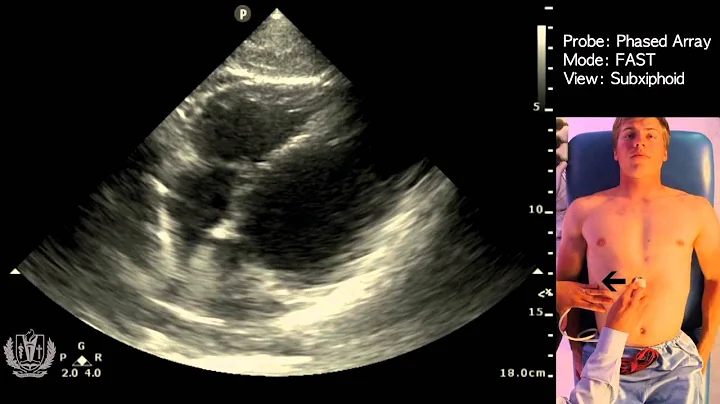

Step by Step instructions on Performing IVC Ultrasound in the Easiest way Possible!